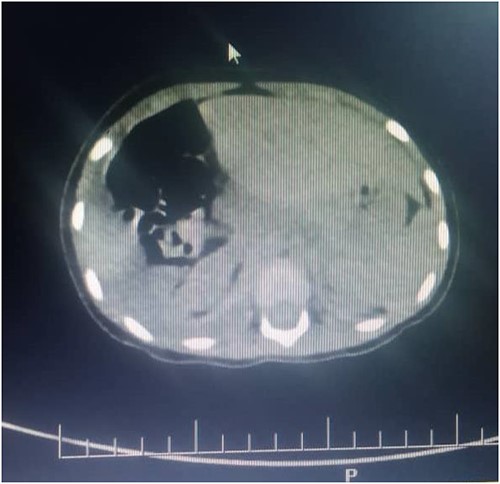

Thus, the tube thoracostomy with under water seal drainage was performed and supportive oxygen therapy was initiated accordingly. In the second day postadmission, the respiratory symptoms resolved and she was weaned off oxygen and other supportive therapies were reduced. Later a whole-body CT scan was performed and admitted in Paediatric Surgery ward in Muhimbili National Hospital. The CT scan revealed a hypodense fluid collection on the right hemithorax, 33HU associated with ipsilateral pulmonary atelectatic changes, discontinuity of the right hemidiaphragm with intrathoracic herniation of the liver that appeared to be normal in size. Nevertheless, the child was in good condition, without respiratory distress or bowel obstruction.

Figures 2 and 3 axial views of thoraco-abdominal CT image taken before laparotomy revealing a ruptured diaphragm of a 1-year-old post trauma patient with reduced right lung volume of expansion.